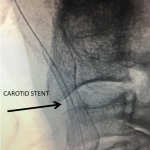

Figure 2.

Catheter angiography prior to angioplasty revealed critical stenosis (Figure 2). Angioplasty was therefore performed under local anesthesia with an embolic protection device deployed to catch any dislodged debris (Figure 3). After angioplasty, a stent was opened across the lesion to maintain long-term patency (Figure 4). Post-stent angiography showed smooth dilatation of the lesion. The patient’s aphasia continued to improve at his 6-week follow-up visit and duplex revealed no significant stenosis through the stent.